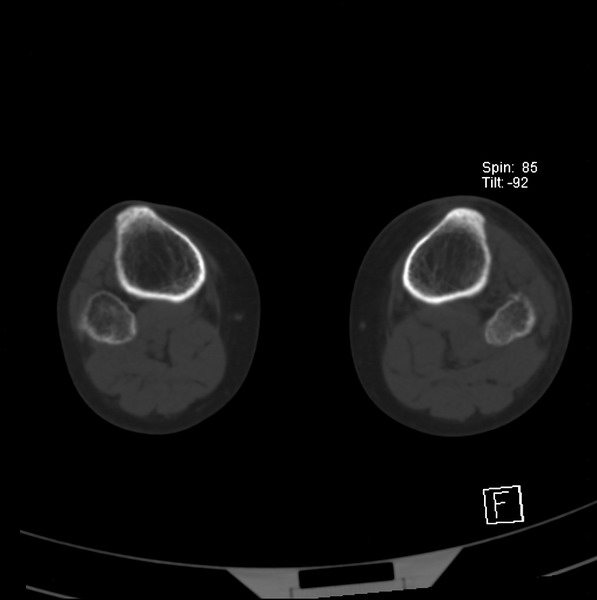

标题: CT21917:右腓骨小头是否骨软骨瘤? [打印本页]

标题: CT21917:右腓骨小头是否骨软骨瘤?

女、43.

不是骨软骨瘤,“牵拽征”,正常变异。有平片吗?

正常变异,“牵拽征”,比目鱼肌牵拽.

比目鱼肌附着点